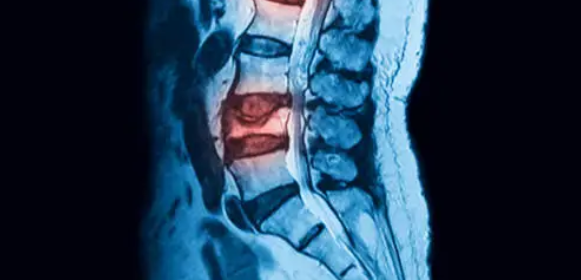

퇴행성 척추질환은 나이가 들면서 척추 구조가 노화되고, 디스크나 척추뼈, 인대 등이 약해지면서 발생하는 대표적인 중장년층 질환입니다. 허리디스크, 경추디스크, 척추관 협착증, 척추전방전위증 등 다양한 형태로 나타나며, 만성적인 통증과 함께 일상생활의 큰 불편을 초래할 수 있습니다. 본 글에서는 퇴행성 척추질환의 원인과 증상, 주요 질환별 특징, 치료법 및 예방 전략까지 종합적으로 안내합니다. 척추 건강을 지키기 위한 첫걸음은 ‘정확한 이해’입니다.

퇴행성 척추질환은 척추의 구성 요소들이 노화되면서 서서히 손상되거나 변형되어 발생합니다. 이 변화는 대부분 서서히 진행되며, 초기에는 특별한 증상이 없지만 점차 통증, 저림, 운동 제한 등 다양한 증상을 유발합니다.

가장 큰 원인은 나이입니다. 40대 이후부터 척추의 퇴행은 본격화되며, 60대 이상에서는 절반 이상이 퇴행성 척추질환을 경험합니다. 척추뼈 사이의 디스크는 수분 함량이 줄어들고 탄력이 떨어지며, 척추를 지탱하는 인대와 근육도 약해지게 됩니다.

퇴행성 변화는 주로 요추와 경추에 많이 발생하며, 다음과 같은 요인이 원인으로 작용합니다.

현대인의 경우 컴퓨터나 스마트폰 사용 증가로 경추에 가해지는 부담이 커져 경추 질환도 점차 증가하고 있습니다. 퇴행성 척추질환은 단순히 노화뿐 아니라 잘못된 생활습관과 근력 부족이 원인이 되는 복합적인 질환이라 할 수 있습니다.